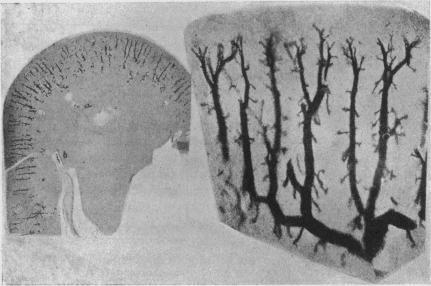

The course of the blood of the renal artery.

https://cdn.ncbi.nlm.nih.gov/pmc/blobs/744a/1514762/de8971370cb3/jphysiol02530-0071-a.jpg

https://cdn.ncbi.nlm.nih.gov/pmc/blobs/744a/1514762/44579e8ce572/jphysiol02530-0070-a.jpg

The course of the blood of the renal artery.肾动脉血液的流动路径。